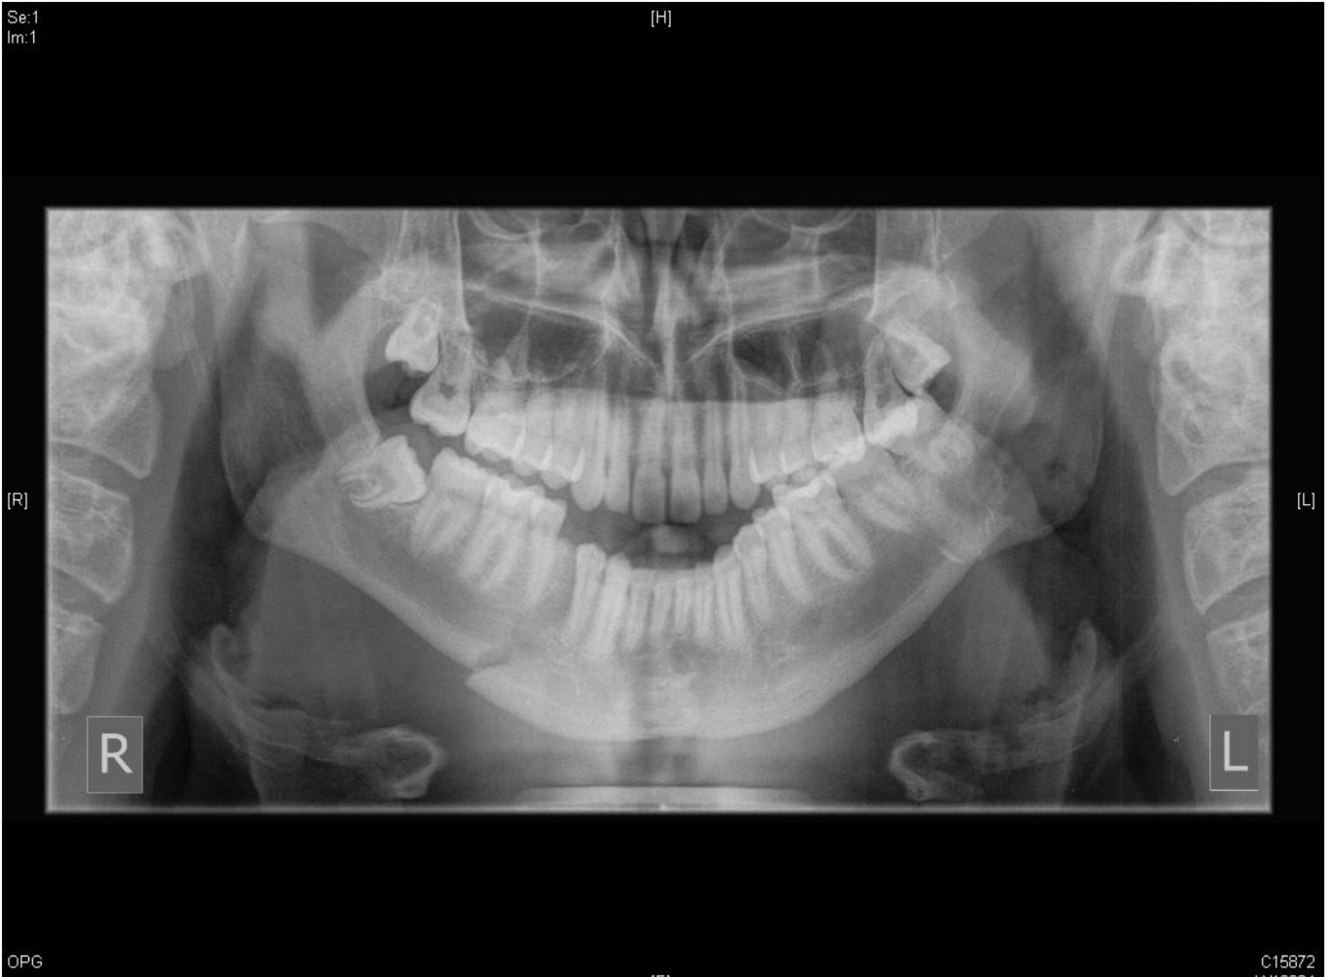

7

Q

abnormalities

A

1. teeth malocclusion

2. fracture body of manible

How well did you know this?